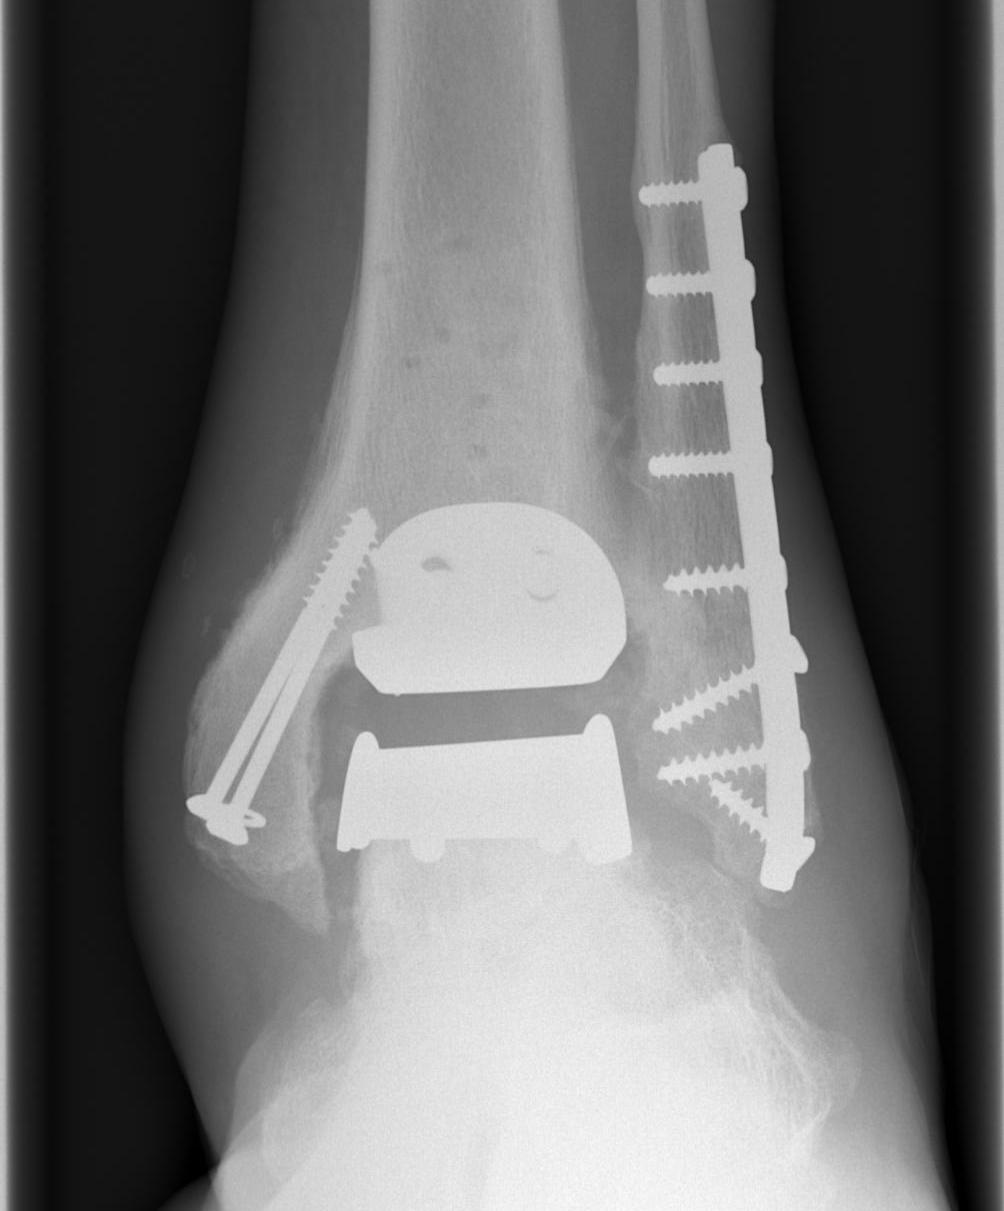

Infinity implant STAR implant Inbone

Agility Salto Tolaris Trabecular metal

B. Lateral approach and fibular osteotomy

Zimmer Biomet Trabecular Metal PDF

Vumedi fibula osteotomy approach for total ankle arthroplasty